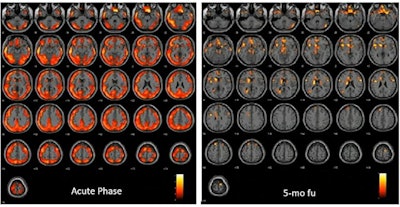

Molecular imaging findings in five patients with FDG-PET scans within two months from the infection showed extended orbital, prefrontal, and temporal-parietal cortex hypometabolism. Three patients with FDG-PET scans five months after the SARS-CoV-2 acute phase showed normal brain metabolism and normal cognitive scores.

- Patients with ongoing SARS-CoV-2 infection featured widespread hypometabolism affecting almost all brain cortices.

- Patients evaluated in post-SARS-CoV-2 infection phase presented with a rather extended cortical hypometabolism only close to the acute phase.

- Along with remission of clinical and cognitive symptoms, the brain hypometabolism reduces progressively as a function of time from acute phase.